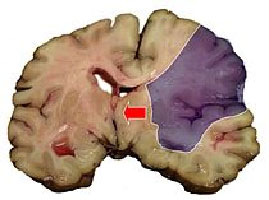

Ишемический инсульт в бассейне средней мозговой артерии. Аутопсия

Фиолетовым обозначена зона инфаркта. Стрелкой показана дислокация срединных структур головного мозга